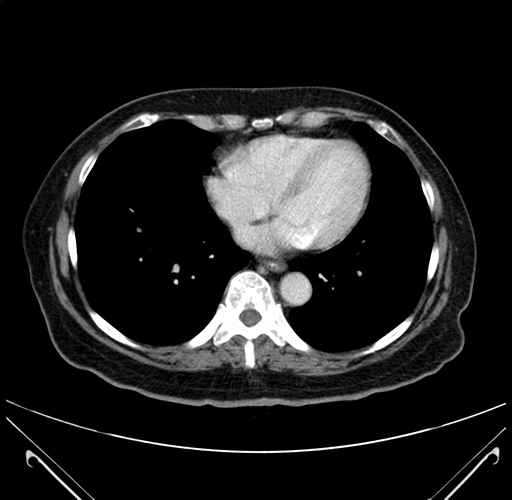

Pre-Chemo: Axial Venous

Axial Venous